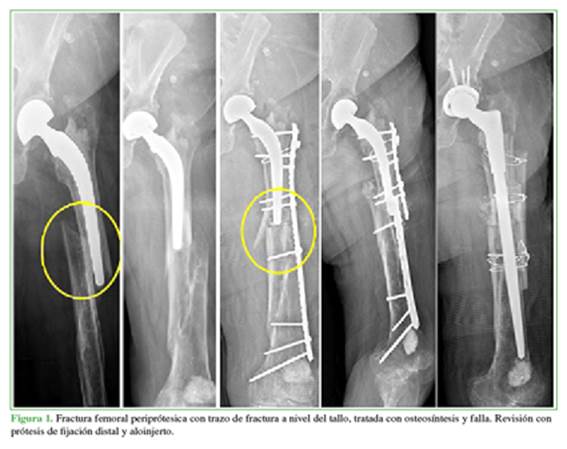

Ninguno de los siete pacientes con retraso de la consolidación requirió de otra operación y la fractura consolidó luego de los controles periódicos y las radiografías seriadas a los 7 meses (4 casos), 8, 9 y 10 meses, respectivamente, el último caso fue una cirugía con requerimiento de aloinjerto. El paciente con trazo de fractura a nivel distal del tallo tratado con una placa lateral bloqueada tuvo una evolución desfavorable con una rotura a nivel del implante y finalmente fue tratado con una prótesis de revisión y fijación distal con aloinjerto, y se logró una correcta consolidación a los cuatro meses (Figura 1). Por último, el paciente con falla de la osteosíntesis fue operado nuevamente con un recambio de la osteosíntesis y aloinjerto; a los nueve meses de la cirugía, había signos de consolidación.